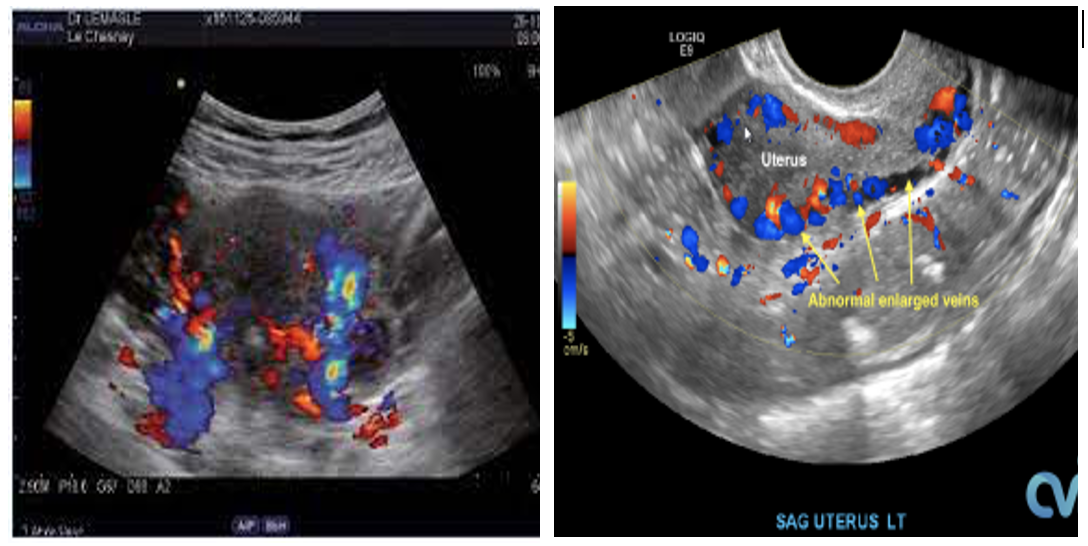

- Xác định nhiều cấu trúc tĩnh mạch giãn xung quanh tử cung (tránh nhầm lẫn với ứ dịch vòi trứng) – chẩn đoán giãn khi đường kính tĩnh mạch quanh tử cung trên 4mm, đường kính tĩnh mạch buồng trứng giãn trên 6mm.

- Vận tốc dòng chảy trong các nhánh tĩnh mạch thấp dưới 3cm/s hoặc có dòng trào ngược sau khi sử dụng nghiệm pháp Valsava (trên 1s).

- Giãn các tĩnh mạch trong cơ tử cung.